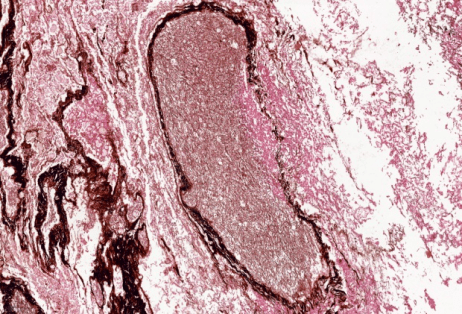

入院后应用导航支气管镜和超声内镜等精准定位技术 , 于右上叶前段、右下叶内基底段取出脓栓 , 并行病理活检:病理可见坏死组织内大量毛霉菌菌丝 , 并可见菌丝侵袭血管(图2) 。 支气管肺泡灌洗液及脓栓二代基因测序(mNGS)显示为微小根毛霉 。最终确定诊断为急性髓系白血病合并肺毛霉菌病 。

文章图片

图2病理显示坏死组织内大量毛霉菌菌丝 , 并可见菌丝侵袭血管(GMS染色及弹力纤维染色)